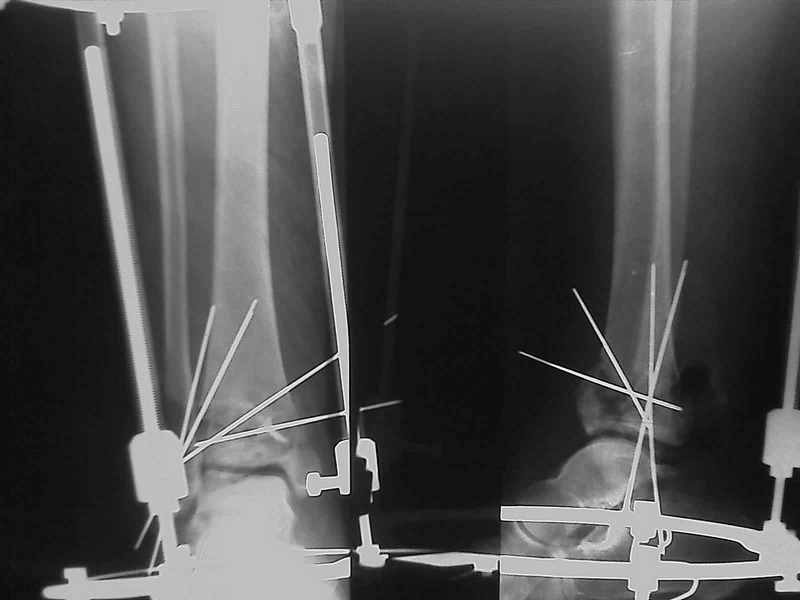

2. Второе. Следует обязательно усилить фиксацию: спицы через передний отдел стопы и пяточную кость, вторая спица через проксимальное кольцо и 1-2 стержня в проксимальный отломок б/б кости. Сроки фиксации до 8 недель. Аппаратом можно устранить, кажется, появившийся вальгус. В подобных ситуациях лучше ведут себя стержни, которыми можно сопоставить и сдавить лодыжки и задний край б/б кости. Привожу случай восстановления голеностопного сустава спустя 2,5 мес.(этап лечения) после травмы со стержнями.

3. Дистальную опору можно было бы взять в виде ¾ кольца или двух разноуровневых полуколец, соединенных небольшими стяжными стержнями. ¾ кольца - не давят на стопу, а разноуровневые полукольца «обходят» сустав. Одно снизу, другое сверху.